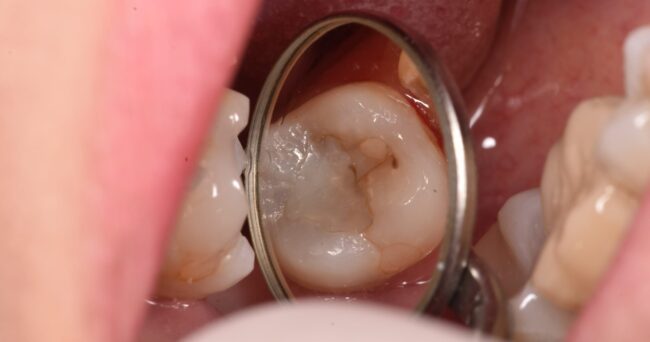

治療前です。

本人に痛みなどの症状はありませんでした。

歯の根元に黒いものが透けているのが、なんとなく見えると思います。

別の角度から見た写真。

ここからは、虫歯がある、という印象は受けないと思います。むしろ、これを見せて「治療します」と言うと「何で??」となる方の方が多いのではないでしょうか?